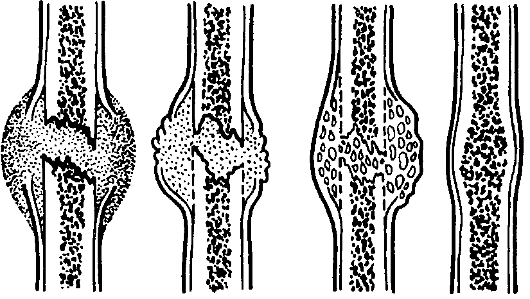

Самая большая проблема, которая возникает при данном виде повреждения – это затруднение сращения, так как оно проходит на фоне патологических изменений костной ткани.

Эта патология также может возникать из-за нарушения целостности костной мозоли, которая формируется после травматического перелома бедренной кости.

- при доброкачественных новообразованиях выполняют резекцию пораженного участка в сочетании с остеосинтезом (скреплением отломков). Если возник большой дефект тканей – проводят замещение алло- или гомотрансплантатом в сочетании с остеосинтезом;

- если диагностировано нарушение целостности диафиза, то поврежденный участок укрепляют костным цементом или замещают дефект трансплантатом.

Костные фрагменты фиксируют с помощью гвоздей, пластин, штифтов, винтов или аппарата Илизарова.